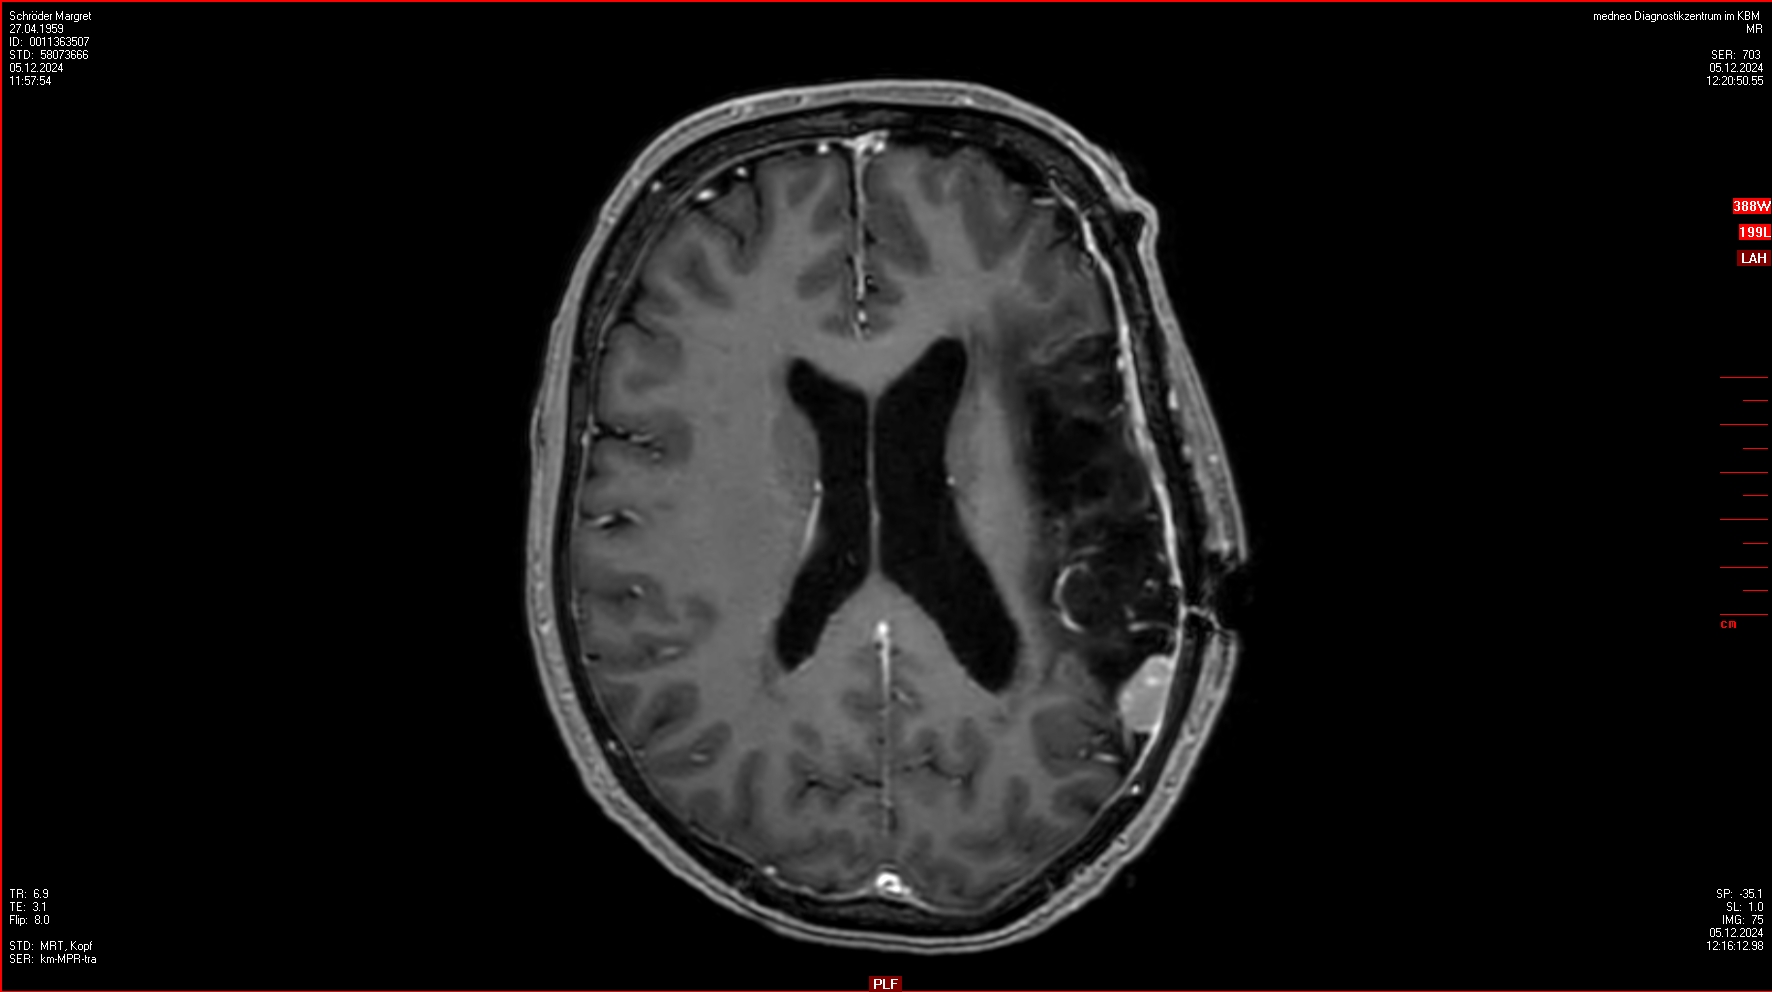

04.12.2024

OP im Krankenhaus Bremen-Mitte: 4 Menigeome (WHO III) entfernt, einige weitere verbleiben.

Ein ausführlicher Bericht von der OP findet sich hier.

23.01.2025

Gamma-Knife Behandlung imICERA Hamburg

4 Menigeome werden bestrahlt.

Ein weiteres Rezidiv wird entdeckt aber nicht bestrahlt. Aber dieses ist in den Folge-MRTs verschwunden.